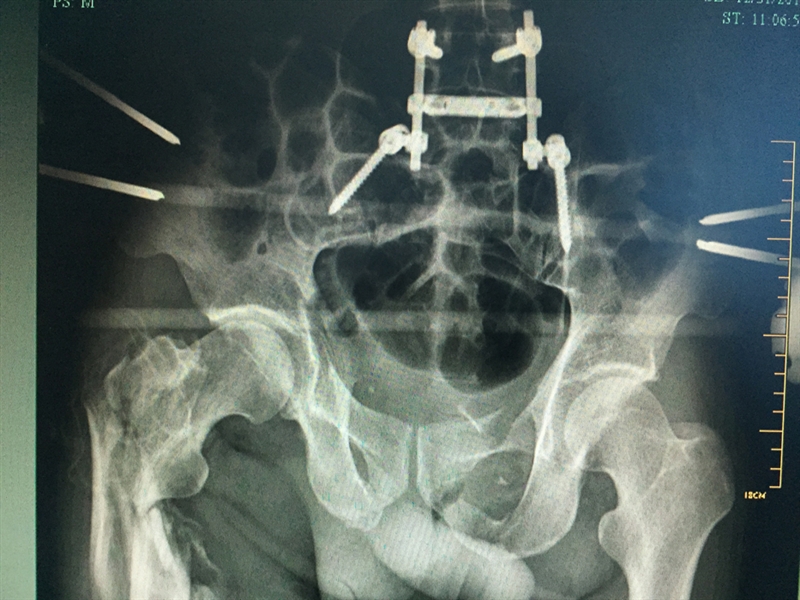

??? 當(dāng)天,張成被轉(zhuǎn)入衢州市人民醫(yī)院救治。到達衢州市人民醫(yī)院之后,緊張的生命接力就開始了,傷情相當(dāng)嚴重,張成生命垂危,重癥醫(yī)學(xué)科(ICU)醫(yī)護團隊立即投入戰(zhàn)斗,進行搶救;生命體征一轉(zhuǎn)平穩(wěn),待命的普外科、麻醉科、手術(shù)室醫(yī)護人員馬上進行脾臟切除術(shù);最后把接力棒交給了骨科,方智敏主任會診后深知這是一個艱巨的任務(wù),隨即帶領(lǐng)診療組探討治療方案,最終制定了詳細的診療計劃,前后對患者進行了三次大手術(shù)……從12月4日至12月31日,短短一個月的時間,張成就接受了五次手術(shù)。

??? 患者術(shù)后的部分X影像